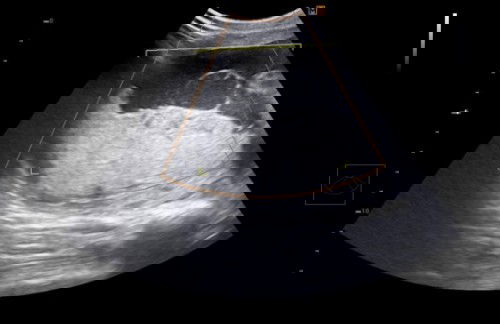

มีใครเคยเป็นก้อนซีสต์ขณะตั้งครรภ์มั้ยคะ

อยากถามแม่ๆท่านอื่น มีใครเคยเป็นก้อนซีสต์ขณะตั้งครรภ์มั้ยคะ ของแม่ตรวจเจอก้อนบริเวณรก ยังไม่มั่นใจว่าใช่ที่รกหรือบริเวณไหน หมอขอเจาะน้ำคร่ำไปตรวจ กำลังรอฟังผล อยากมาสอบถามมีแม่ๆคนไหนมีประสบการณ์แบบนี้มั้ยคะ อันตรายกับลูกมั้ย#ขอคำแนะนำหน่อยค่ะ